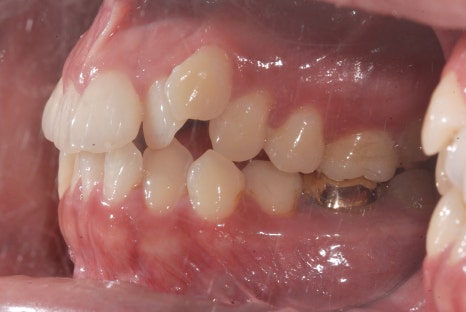

<교정치료 전후 사진>

치료기간: 23.05.15 - 24.10.21 (약 1년 6개월)

진행한 치료: 덧니, 치열 개선

*치료 전후 사진은 환자의 동의하에 게재하였으며, 동일한 환경과 조건에서 촬영된 전후 사진입니다.